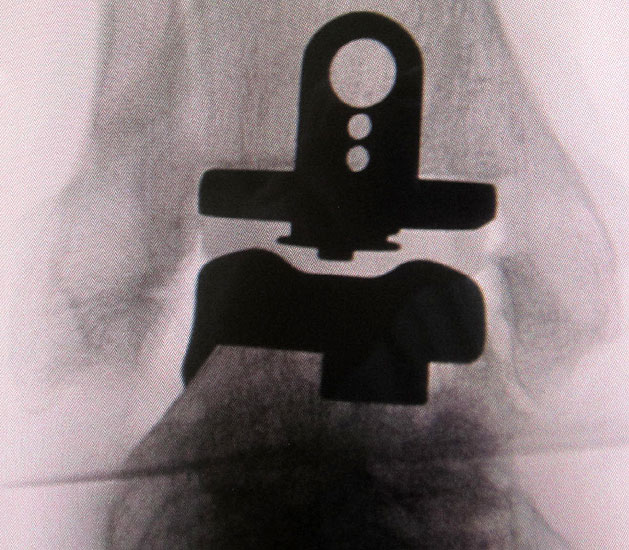

Das Operationsprinzip umfasst eine minimale Knochenresektion mit zementfreier Implantation der Prothesenkomponenten am oberen Sprunggelenk.

Ein anatomisches Komponentendesign mit der Möglichkeit von Seit- und Rotationsbewegungen des Talus in der Malleolengabel spiegelt am besten die normale Biomechanik eines Sprunggelenkes wider (Hintermann 2005).

Voraussetzungen für eine langfristige stabile knöcherne Verankerung der Komponenten sind eine möglichst große Kontaktfläche zwischen Implantat und Knochen in der subchondralen Zone sowie die Vermeidung der Schwächung der kraftübertragenden Anteile der distalen Tibia. Dies betrifft insbesondere die ventrale Kortikalis der Tibia (Hintermann 2005).

Die Schaffung einer hohen Kongruenz mit mechanisch stabiler Führung zwischen dem Polyethylen (PE)-Inlay und den metallischen Komponenten dient der Vermeidung eines komponentenbedingten PE-Abriebes. Die achsgerechte Prothesenimplantation sowie die Wiederherstellung einer stabilen und physiologischen Rückfußeinstellung durch zusätzliche korrigierende und stabilisierende Operationen (Osteotomien, Sehnentransfers, Bandplastiken, Arthrodesen) sind Voraussetzungen für die Vermeidung eines frühzeitigen Polyethylenverschleiß bzw. Komponentenlockerung (Hamel, 2006).